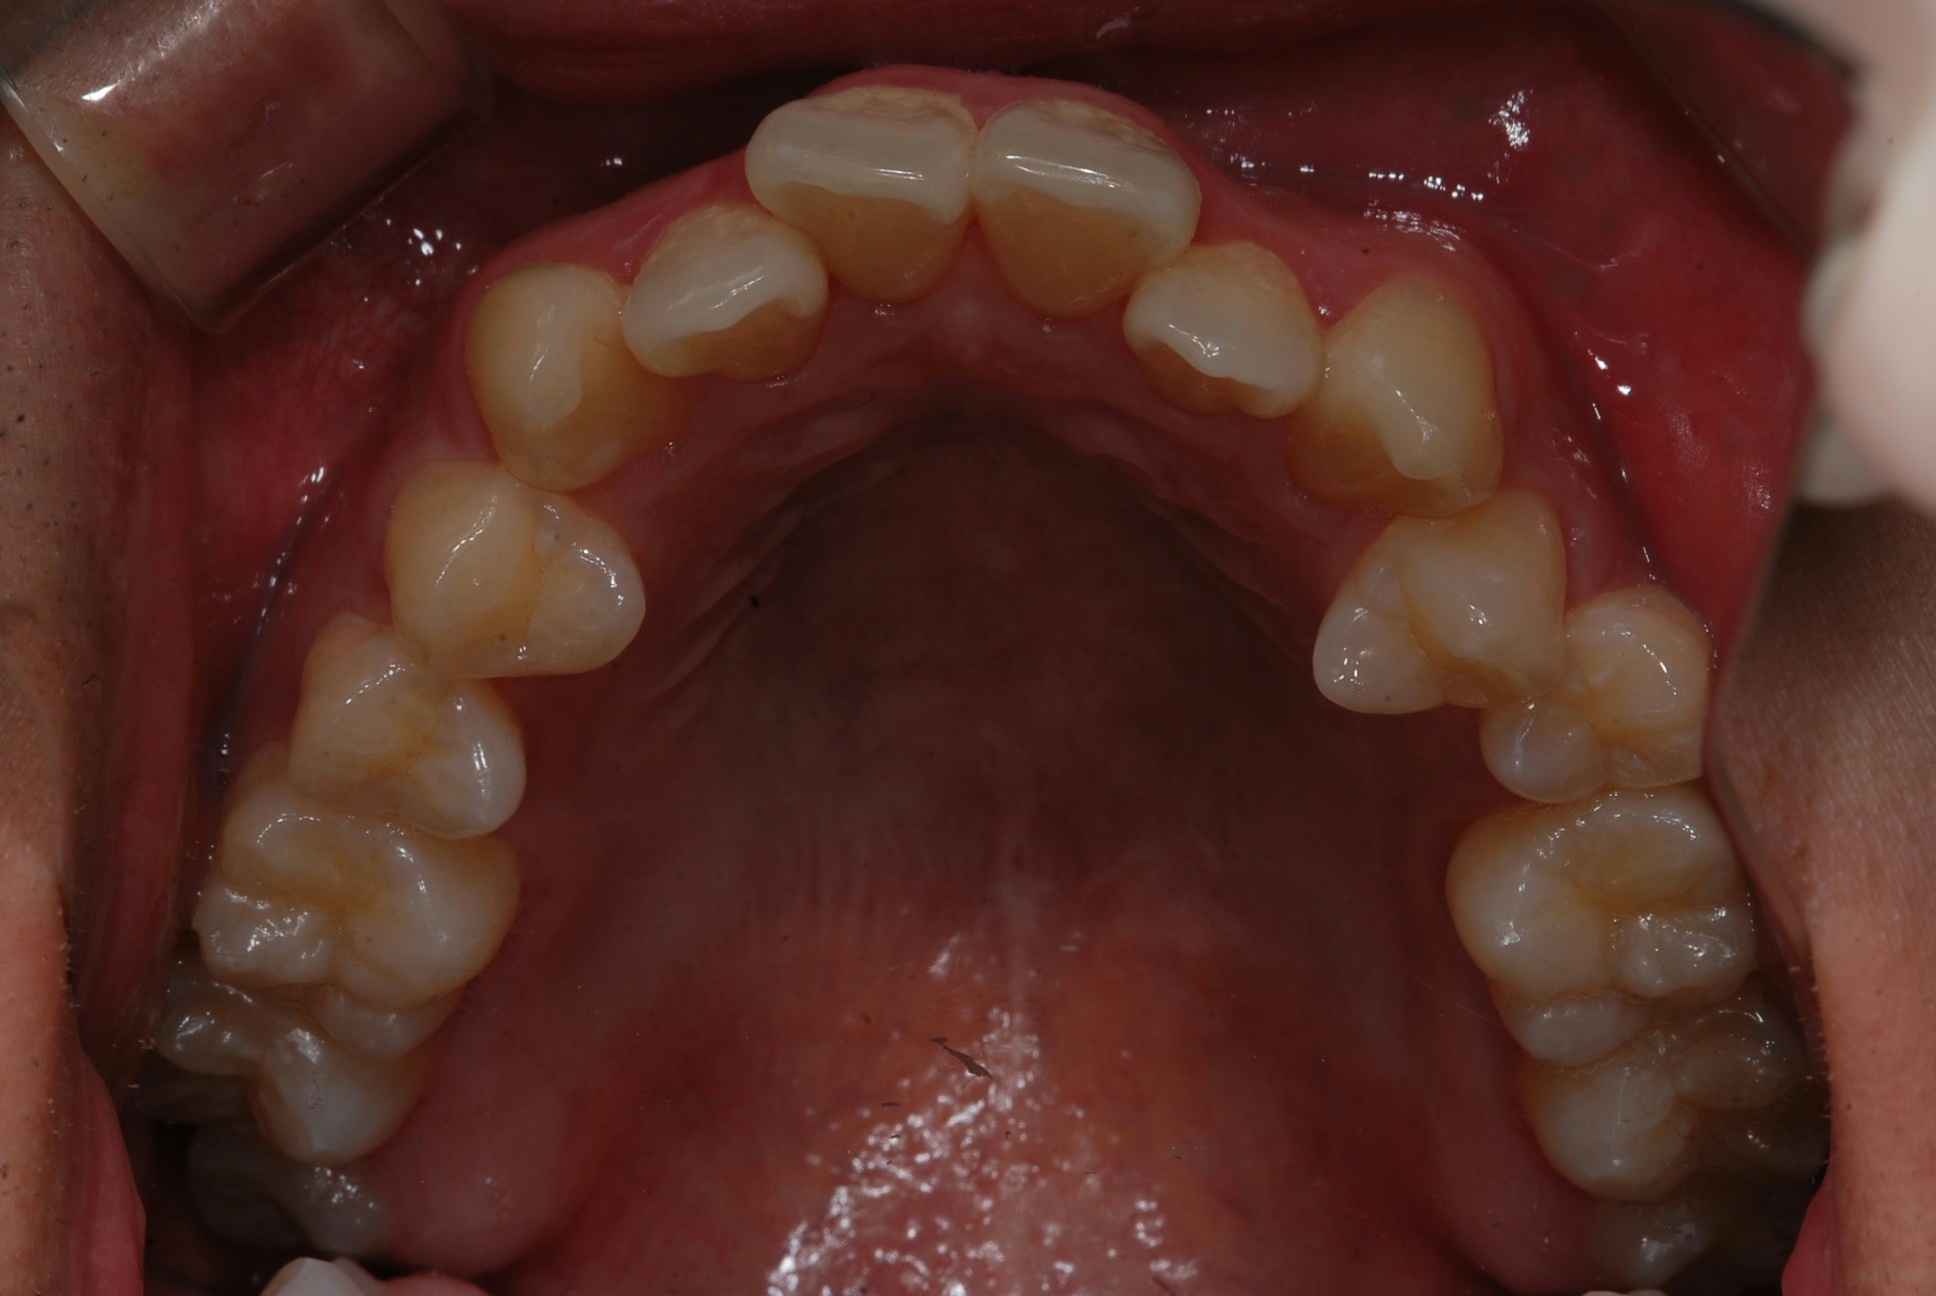

치료 전 사진입니다.